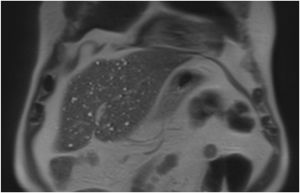

Se realizó una tomografía abdominal por antecedente del paciente y se evidencia una fuga protésica grado II. La ecografía abdominal demostró paredes vesiculares engrosadas. La colangiorresonancia mostró imágenes sugestivas de cuerpos de Von Meyenburg y ausencia de obstrucción biliar (figs. 1 y 2). El paciente evoluciona favorablemente y continuó con vigilancia clínica ambulatoria.

Los hamartomas biliares múltiples (HBM) son malformaciones benignas raras de los conductos biliares intra-hepáticos; descrito por primera vez por Von Meyenburg en 19551. Los HBM aparecen en el 0,9% de los niños y en el 5,6% de los adultos. Se puede visualizar un artefacto de «centelleo», debido a las reverberaciones que producen los cristales de colesterol que llenan los conductos dilatados. La resonancia magnética proporciona una mayor sensibilidad y especificidad2. El HBM es una enfermedad asintomática, benigna3 y no requiere tratamiento específico.